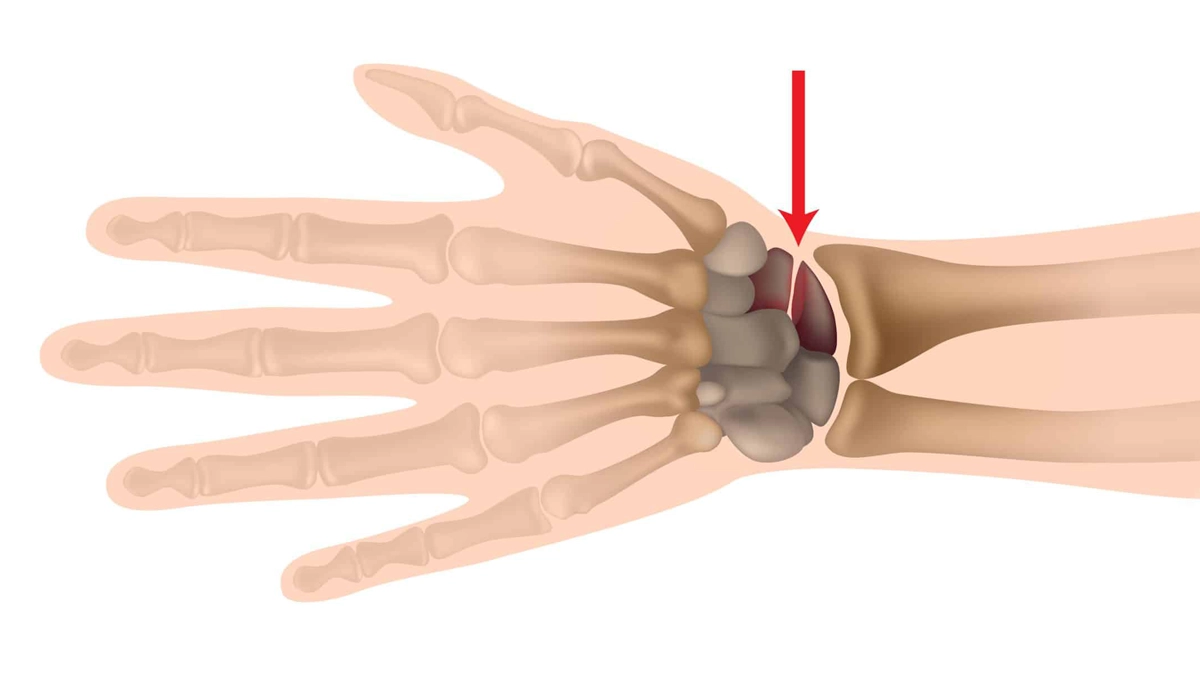

Skafoid kemiği, el kemikleri ve ön kol arasındaki bağlantıyı sağlayan sekiz karpal kemikten biridir. Bu kemik, anatomik olarak önemli bir rol oynar çünkü elin hareket kabiliyetine katkıda bulunur. Skafoid kemiği, el bileği bölgesinde yer alır ve bu bölgedeki diğer kemiklerle birlikte, elin stabilitesini ve işlevselliğini artırır. Özellikle günlük yaşamda elin hareketleri sırasında, yük taşıma ve denge sağlama gibi işlevlerde kritik bir öneme sahiptir.

Skafoid kemiği, ön kola ve ele yakın iki sıra şeklinde bulunduğundan sık sık travmaya maruz kalmaktadır. Skafoid kırığı, el bileği üzerine direkt olarak düşme sonucunda oluşabilir. Bu kırığın en büyük sebebi, düşme gibi travmatik durumlardır. Özellikle sporcular, özellikle de kaykaycılar ve dağcılar, bu tür yaralanmalara daha yatkındır. Düşme anında, el bileğinin pozisyonu ve düşüş açısı, yaralanmanın şiddetini etkileyen faktörlerdir. Düşme sırasında elin yere doğru açılması, skafoid kemiğinde kırığa neden olabilir ve bu durum, hastanın günlük yaşamını ciddi şekilde etkileyebilir.